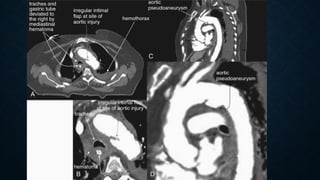

• Grading

• Thoracic aortic injury can be graded according to the severity of

injury. One grading system is

• grade 1: intimal tear

• grade 2: intramural hematoma

• grade 3: pseudoaneurysm formation

• grade 4: free rupture

Indirect signs of aortic injury:

Mediastinal hematoma

Periaortic fat stranding

CT Angiography:

100% sensitivity and specificity

Signs of mediastinal hematoma

Abnormal soft tissue density around mediastinal structures

Location – periaortic hematoma than isolated mediastinal hematoma remote from the

aorta.

SIGNS OF AORTIC

INJURY:

Intraluminal filling defect (intimal

flap or clot)

Abnormal aortic contour (mural

hematoma)

Pseudoaneurysm & extravasation

of contrast